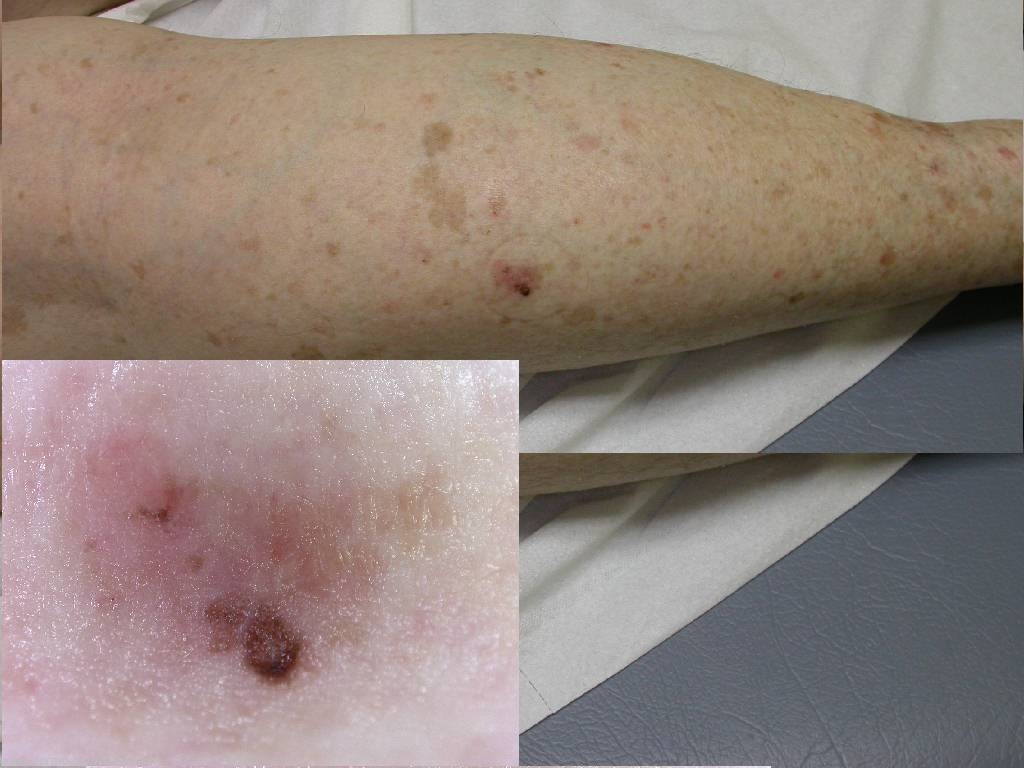

This was the December 2007 Dirty Dozen composed by Dr Tim Hackett. Case 1 72 year old female with a lesion noted on the lower leg. Present for many years according to patient.

Question: What is the diagnosis? Consider Melanoma, Seborrhoeic keratosis, Pigmented IEC, Pigmented BCC, Dysplastic nevus.